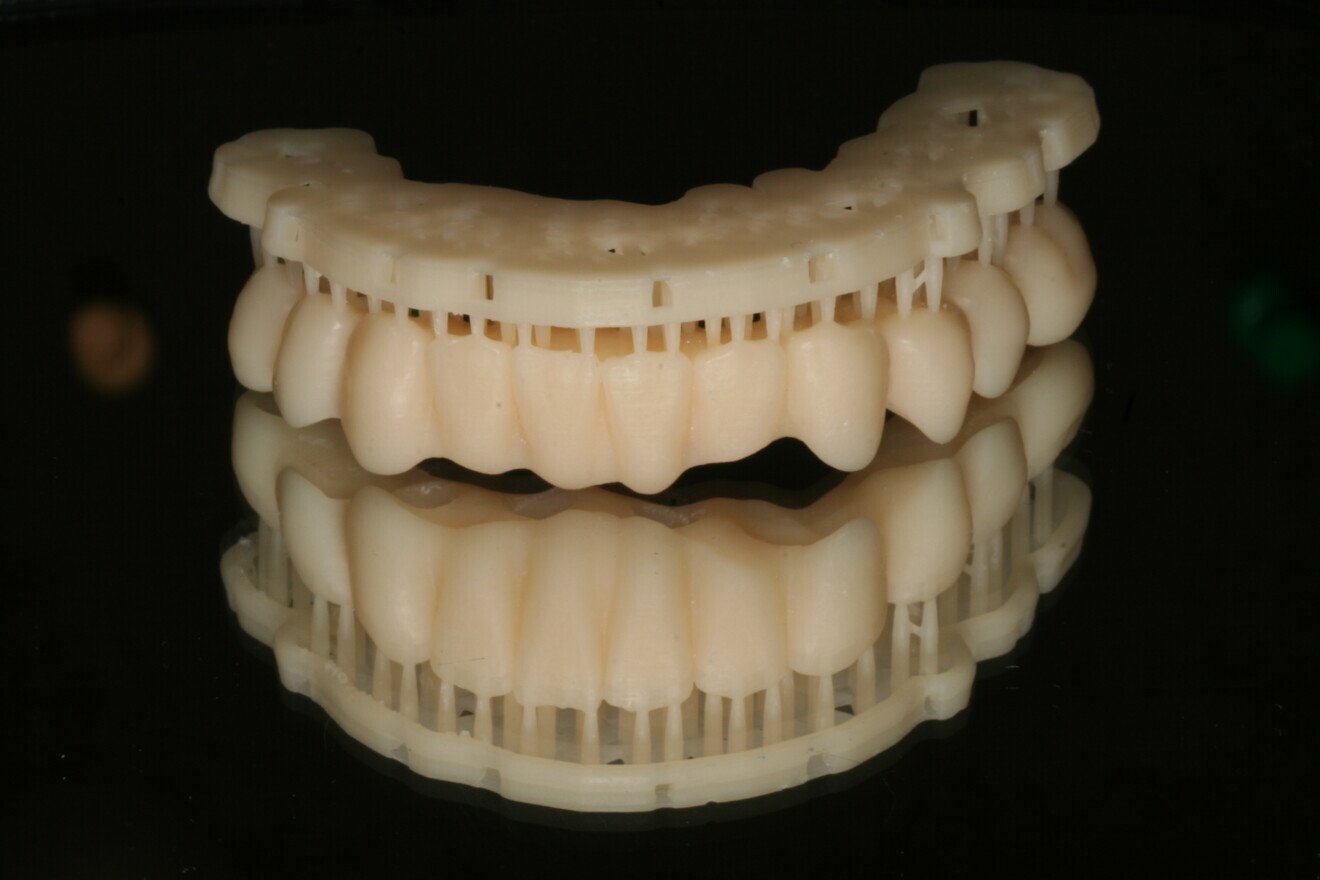

Fig. 8: 3D-printed temporary restoration.

Digital impressions were taken with CEREC Primescan (Fig. 7) and sent to the laboratory for same-day fabrication of the temporary restoration (Flexcera Smile Ultra+, Desktop Metal; Fig. 8). Suturing was completed, and the full-arch temporary restoration was adjusted and seated with temporary cement (Fig. 9).